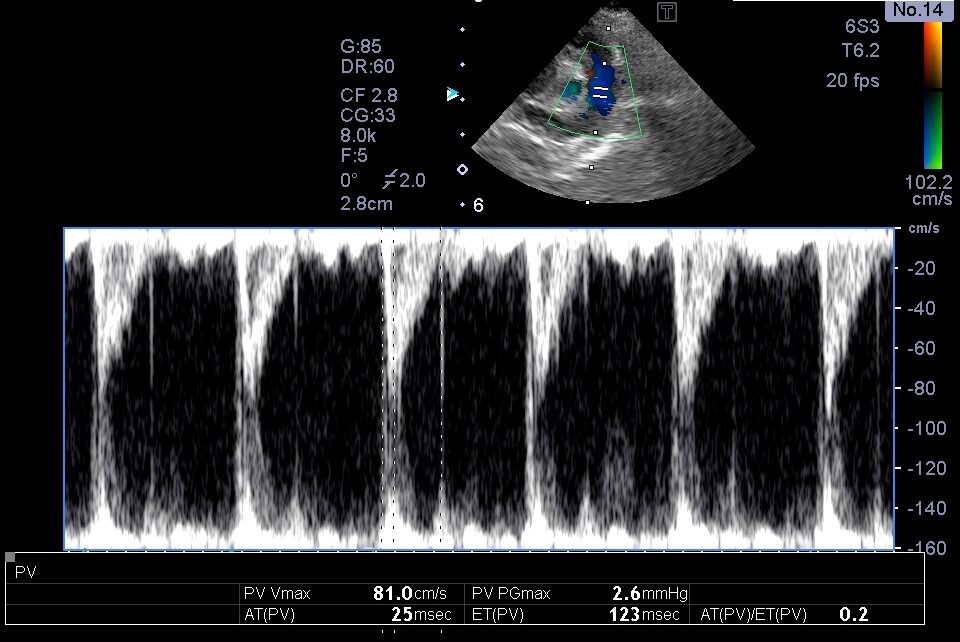

肺動脈血流の加速時間短縮

胸部超音波検査では、上記のような肺高血圧症による心臓の変化が認められました。

これらの所見から、現在の投薬では肺高血圧症のコントロールが難しいと判断し、利尿剤の追加とシルデナフィルの増量を行いました。